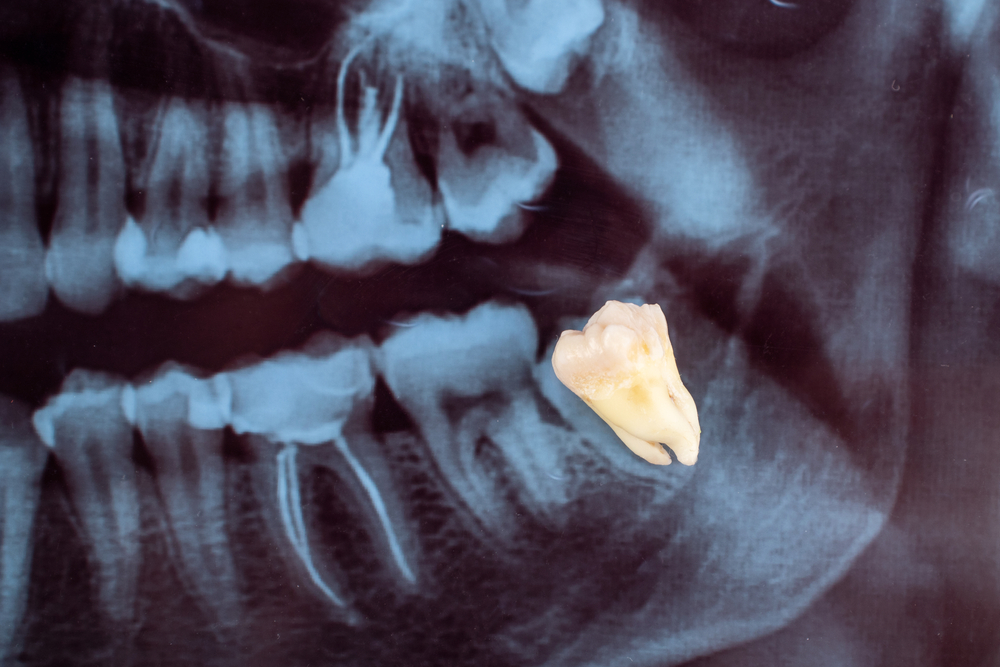

When is a Tooth no longer salvageable and extraction is necessary?

Where possible a dentist will always attempt to save your tooth from extraction using root canal therapy or other dental techniques. In some cases where the decay too great from cavities caused by the long term build up of bacteria, the deepest layers of pulp within the tooth have become infected and the tooth is no longer salvageable. Similarly, where fractures or cracks have occurred and too much of the tooth is lost a crown may be unable to be fitted and thus root canal therapy is no longer an option the tooth must be removed to avoid further pain and damage within the mouth and jaw.

What does wisdom tooth extraction involve?

The removal of upper wisdom teeth is generally regarded as easier than the lower and most can be removed easily under general anaesthetic. The removal consists of making an incision in the gum to reveal the wisdom tooth, removing the bone fragments that obstruct the tooth’s root and dividing the tooth with a drill into more manageable pieces for ease of removal.